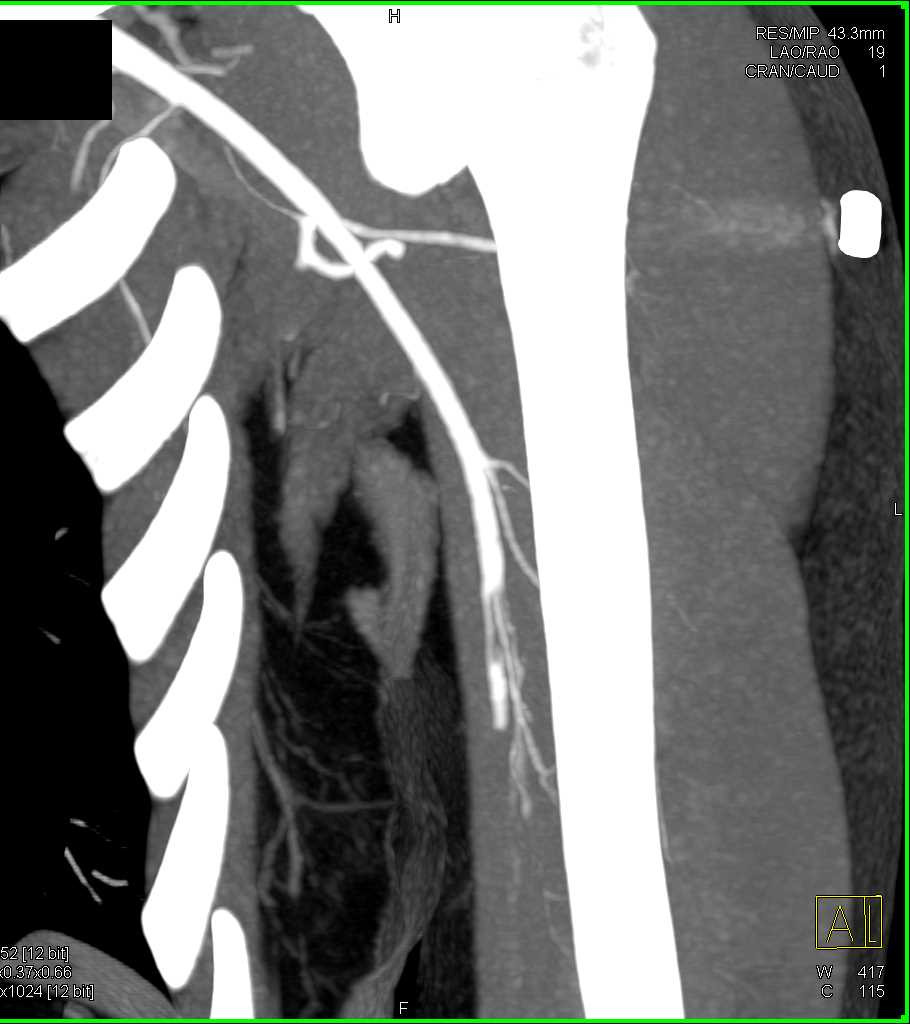

Brachial Artery Occlusion